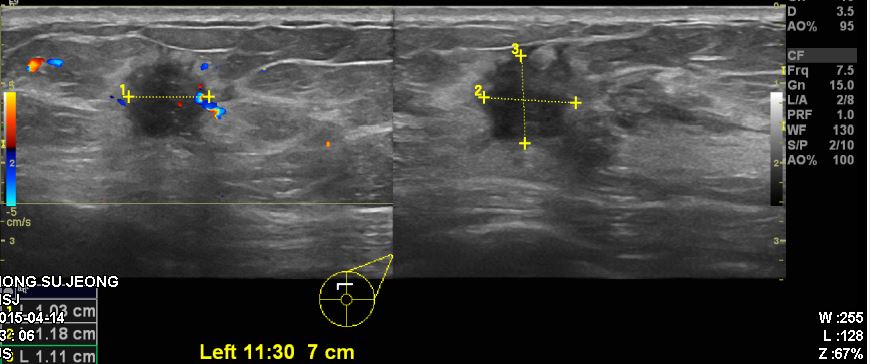

좌측 유방에 만저지는 몽우리 있어 내원하신 60대 여성 분으로 좌측 침윤성유관암 진단되었으면 겨드랑이 전이로 확인 되었습니다.